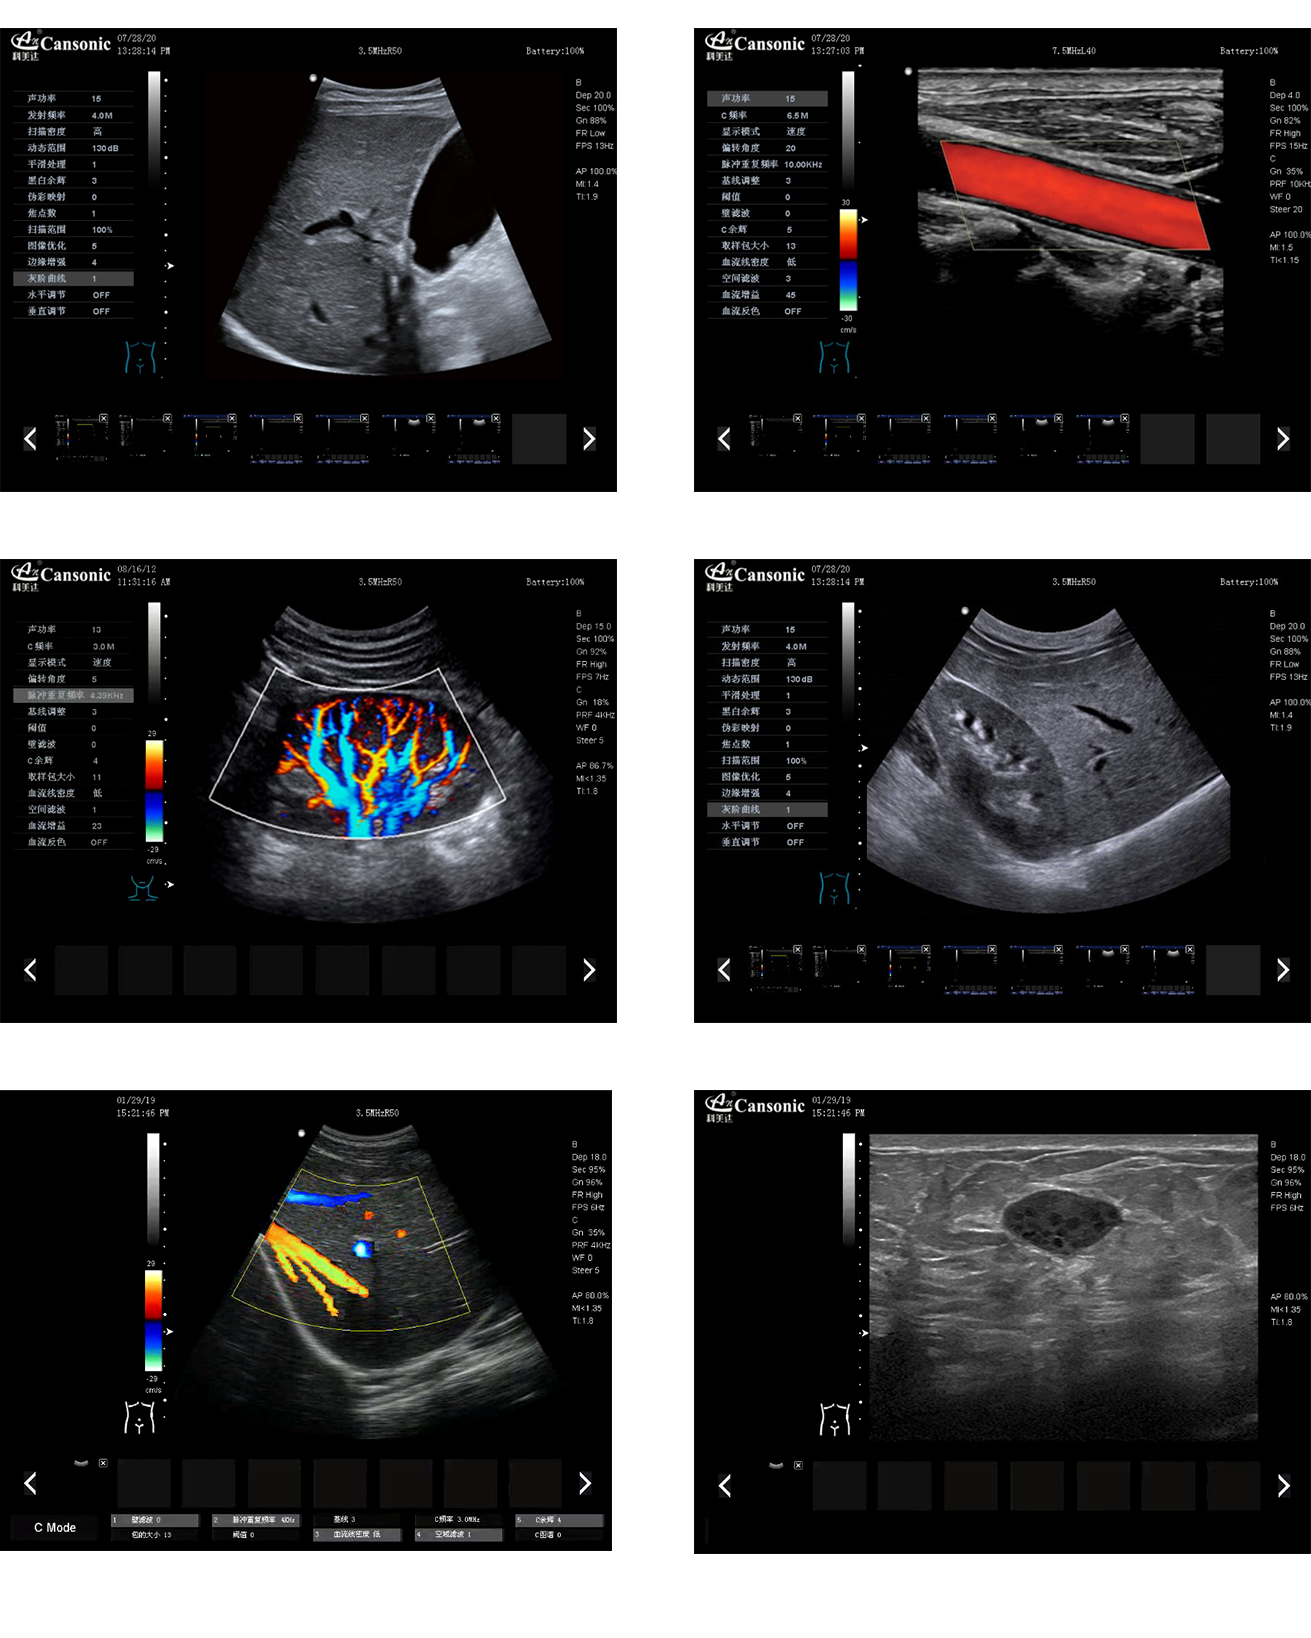

科美達K8圖像實例

1、全新一代便攜彩超,采用高端彩超技術(shù),提供完整的臨床解決方案,適應(yīng)各種臨床環(huán)境

2、圖像細膩,質(zhì)量優(yōu)異,同時性能穩(wěn)定,每天能做大量檢查

3、選擇手動或自動包絡(luò)頻譜,一鍵顯示各種血流動力學(xué)數(shù)據(jù)

4、高分辨率灰階血流成像,明顯提升對微細血管的血流探測能力,對大血管管壁成像及管壁斑塊的診斷有著很大幫助